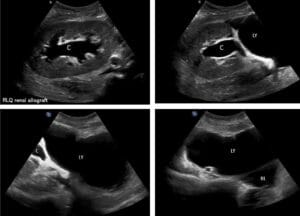

On admission, vital signs were within normal limits. His abdomen was non-tender to palpation without palpable masses. The site of the prior right nephrostomy tube site was unremarkable. A Foley catheter was draining clear yellow urine. Laboratory work-up was significant for leukocytosis (28.2 x 103/µL), blood urea nitrogen 80 mg/dL, and serum creatinine 4.85 mg/dL. Urinalysis was significant for >100 white blood cells and red blood cells and a “few” yeast per high powered field. On arrival, renal point of care ultrasound was done. The left kidney had no structural abnormalities. On the right, a perinephric anechoic fluid collection was seen, no hydronephrosis was present (Figure 1, online Video S1). Interventional radiology (IR) ultrasonographically confirmed these findings. Under fluoroscopy, IR injected contrast via the prior nephrostomy tube tract and contrast reached the perinephric fluid collection. A percutaneous drain was inserted into the fluid collection with return of ~30 mL of purulent fluid. Blood cultures grew Pseudomonas aeruginosa and Candida glabrata. Creatinine from the fluid collection was 4.2 mg/dL (serum creatinine was 4.3 mg/dL). The perinephric fluid collection grew Escherichia coli. He was started on micafungin and cefepime. One day later, repeat ultrasound showed resolution of the anechoic fluid collection (Figure 2). Creatinine returned to baseline and the patient was discharged on fluconazole and cefepime to complete his treatment course. He was seen two weeks after discharge in clinic and was doing well, at which time the drain was removed.

Figure 1. Right kidney in long-axis with perinephric abscess.

Figure 2. Right kidney in long-axis, after drainage of perinephric abscess.